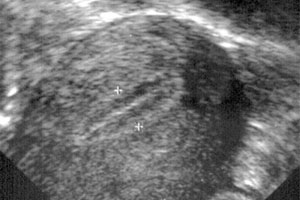

• Ultrasound imaging: Transvaginal ultrasound is widely used to measure uterine dimensions, evaluate the myometrium and endometrium, and detect abnormalities such as fibroids or polyps.